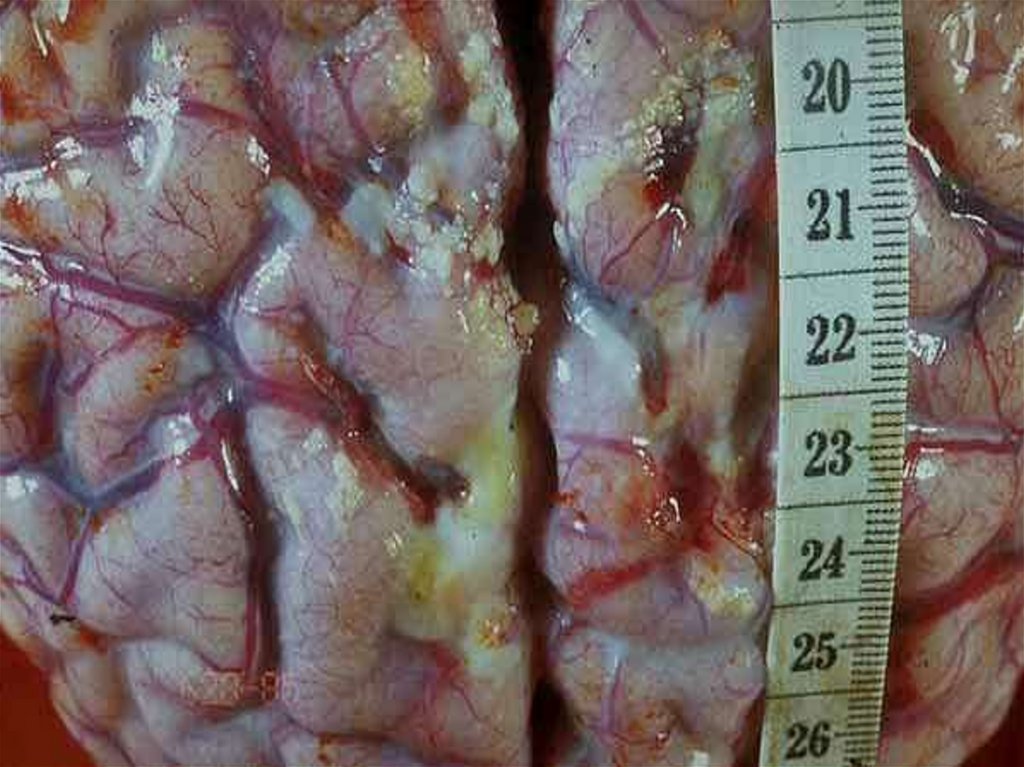

ПАТОМОРФОЛОГИЯ

– N.m. вызывают острую воспалительную

реакцию в месте внедрения.

Эндотоксемия приводит к диффузному

васкулиту и ДВС-синдрому,

Кровеносные сосуды заполняются сгустками

крови с большим содержанием фибрина и

лейкоцитов, что приводит к кровоизлияниям во

всех органах, но на коже они наиболее заметны

и часто сопровождаются некрозами в центре

крупных элементов.